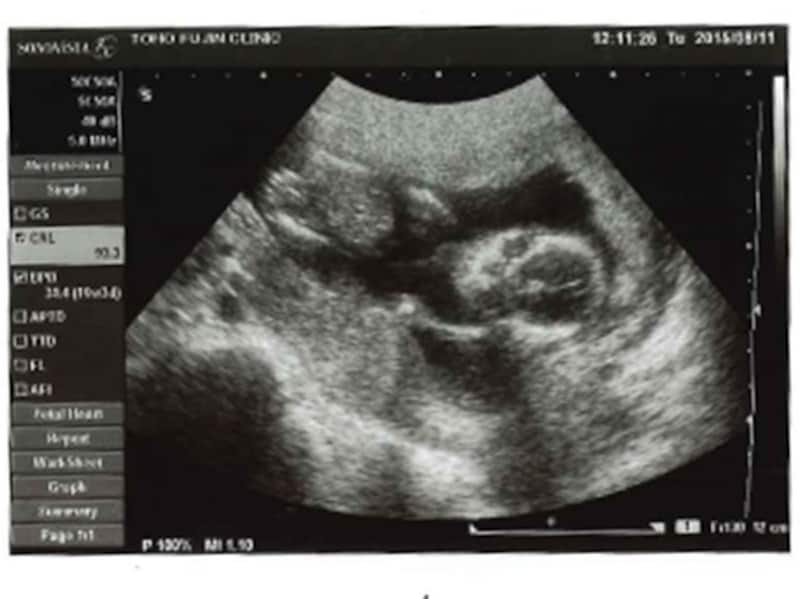

妊娠16週 赤ちゃんの性別が分かる人も!胎児の大きさ・エコー写真

妊娠17週目エコー写真・胎児の大きさ・胎動や性別が分かることも!

妊娠18週目エコー写真・赤ちゃんの大きさ・胎動が分かる人も

妊娠19週目 胎動や性別が分かる人も!胎児のエコー写真・大きさ